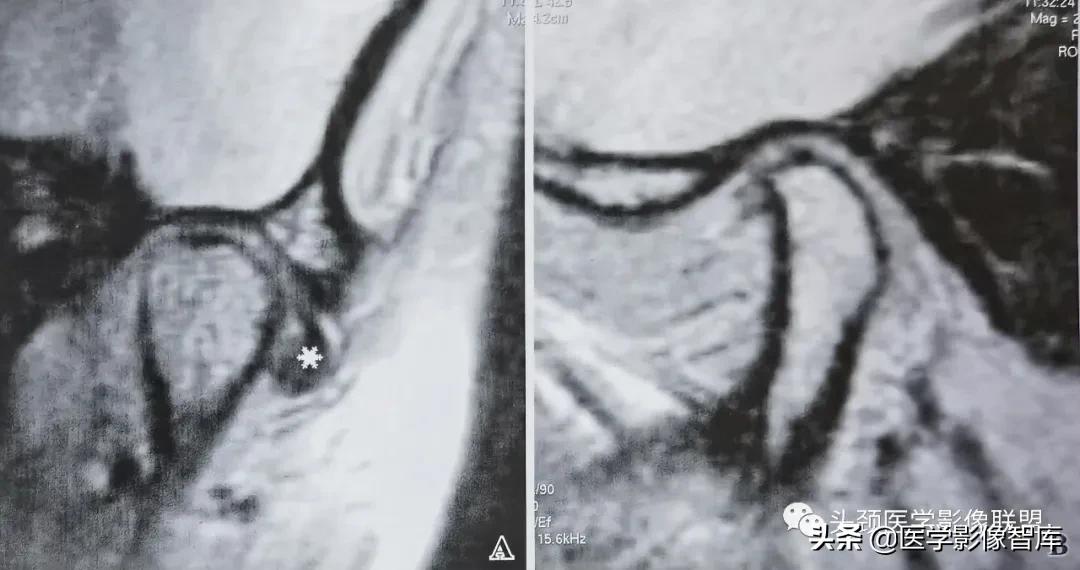

图3 不可复性关节盘前移伴盘变形

A. 矢状面闭口PDWI示:关节盘后带(黑星)位于下颌髁突前方;B. 矢状面开口T2WI示:关节盘随下颌髁突前移,仍位于其前方。开闭口位上均见关节盘呈变形改变:关节盘前带弯曲折迭,关节盘后带相对增厚。下颌髁突活动度小。

关节盘变形主要出现在不可复性盘移位中。变形的关节盘可以出现在闭口位上,也可以出现在张口之后。张口时的关节盘变形明显多见,主要是关节盘受向前运动之下颌髁突挤压所致。MRI上,变形的关节盘失去正常时双凹形或蝶结状轮廓,可以呈多样性表现,如关节盘前带弯曲折迭,关节盘后带增厚,盘后双板区纤维化和伴有盘中带缩短的盘后带增大等。由于下颌髁突在张口前移时受到前方关节盘的阻挡,故在MRI上常能显示下颌髁突活动受限。此时,下颌髁突之大部仍位于颞骨关节窝内,不能到达关节结节的下方或前下方 (图3) 。